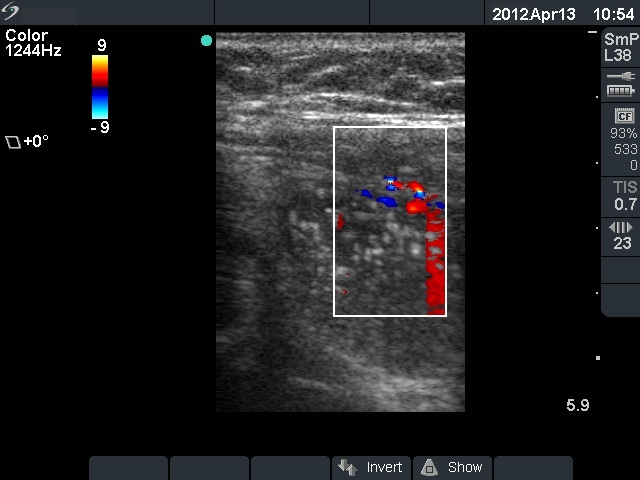

Second examination 14 months later (second row of images)

The whole thyroid increased in volume by 38%. Surgery was advised

Histopathology: benign hyperplastic nodular goiter.